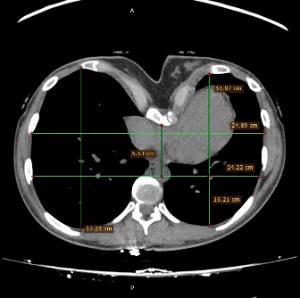

Pectus Excavatum Pectus Excavatum Asimétrico Índice de Asimetría 0.6 (+R/-L)(|AI|> 0.05 Asimétrico) Índice de Haller 4.5 (HI >3.5) Índice de Corrección 49.13% Rotación esternal 18.1 ° (a la derecha)

Informe d'avaluació del TAC d'un pacient enviada al cirurgià